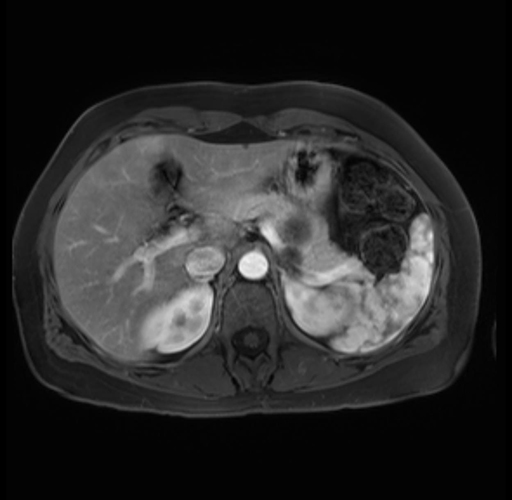

Imaging Analysis

Look through the patient's CT scan to identify any areas of concern for the necessary procedure.

Based on your CT findings, which issue(s) are present and would give reason for "planned slowing down moment(s)" in this case?